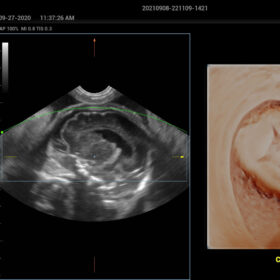

- Smart Scene 3D – Full Stack smartness obstetric solution empowered by ZST+. Comprehensive 3D/4D OB imaging solution with comprehensive fetal parts coverage.

One Key for favorite fetal part imaging, reducing manual adjustment - Smart Face – Automatic removal of occlussions over fetal face with one click

- Smart FLC 2D/3D – Automatic Follicle Counting and measurements in 2D/3D mode